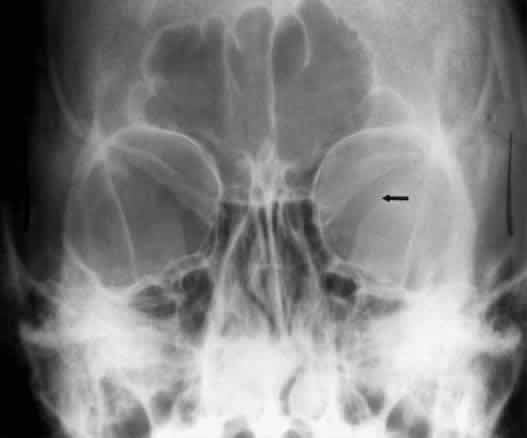

The orbital floor consists of the maxillary, zygomatic, and palatine bones. The floor is thinnest medial to the infraorbital canal, which is the location of most orbital floor fractures (Fig. 7). As mentioned earlier, the floor slopes upward from the lateral to the medial wall. The floor extends toward the orbital apex but does not reach the apex. This orientation of the floor makes frontal projections more informative than the lateral projection.

Fig. 7. A patient involved in a motor vehicle accident who sustained a right orbital floor fracture. Soft tissue density (arrow) located in the roof of the maxillary sinus. Disruption of the orbital floor is seen at the fracture site.

Waters view gives the best image of the anterior and middle portion of the floor. This is possible because extension of the neck brings the floor into a position that is tangential to the x-ray beam. The floor is represented by the most inferior radiopaque line, whereas the orbital rim will be the line above it.10 The vertical distance between these lines should be approximately 1 cm.19 This relationship between the floor and the orbital rim should be symmetric between the two orbits. Any asymmetry should suggest a fracture of the orbital rim or floor.